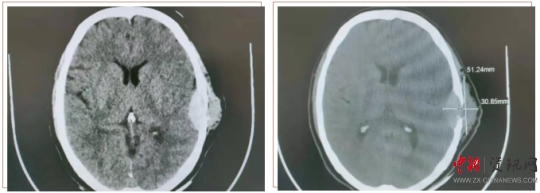

患者王某,女,58歲。半年前,患者用手觸摸頭部左耳上側(cè)時,發(fā)現(xiàn)一個小腫物,如花生米大小,當時沒太在意,十幾天前發(fā)覺腫物突然增大,由原來的1cm左右增大至5cm左右,且有壓痛感。于是來到上蔡縣人民醫(yī)院就診。神經(jīng)外科副主任楊學義接診后,安排患者做顱腦CT檢查,結(jié)果顯示:左側(cè)顳部占位侵犯腦膜及顱骨骨板,需要手術(shù)治療。遂收入神經(jīng)外科,經(jīng)過充分的術(shù)前討論,制定周密的手術(shù)方案后,由神經(jīng)外科主任周學良、副主任楊學義、主治醫(yī)師商文山、楊慶華歷時3個小時,成功將患者左側(cè)顳部5×4cm腫瘤完全切除,同時行“硬腦膜修補、顱骨修補手術(shù)”,術(shù)中精準解剖,精細操作,避免了血管及神經(jīng)等副損傷。術(shù)后顱腦CT掃描顯示:腫瘤完全切除,無腫瘤組織殘留;颊攥F(xiàn)已痊愈出院,未出現(xiàn)神經(jīng)功能障礙。目前正在隨訪中。

顱腦 CT 掃描顯示(下圖):左側(cè)顳部占位侵犯腦膜及顱骨骨板。